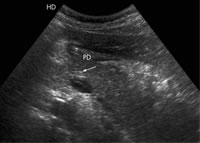

图1(3.5 MHz凸阵探头腹部超声图像)所示,在十二指肠降段内,可见一个长管状匍行性病变(实时显像见病变可移动),病变部分位于主胰管内,胰头部肿大。图2显示的是高频超声图像(7.5 MHz线阵探头),提示管状病变为一条蛔虫。

图1 3.5MHz凸阵探头腹部超声图像显示,在十二指肠降段存在一个长管状匍行性病变,病变部分位于主胰管内,胰头部肿大

图2 7.5MHz高频线阵探头腹部超声可见管状病变